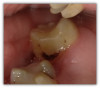

Figure 8a and Figure 8b show a terminal abutment with proximal decay from a removable cast metal partial denture. The tooth had an existing large resin restoration that was otherwise stable and the decay was isolated to the mesial surface. The patient had limited funds, and while a crown was presented as a restorative option, the patient elected to restore the tooth with a direct restoration at the time. The composite used was the Tokuyama Omnichroma. The practitioner excavated the decay and much of the filling. In this scenario, using a flowable bulk fill with self-settling and blendable properties that also does not require a capping layer, proved advantageous in restoring the tooth's contour, making it easy to retrofit the RPD.

Fig 8a. A terminal abutment with proximal decay from a

removable cast metal partial denture. The composite used was

Tokuyama Omnichroma flow bulk.

Fig 8a.

Fig 8b. A terminal abutment with proximal decay from a

Fig 8b.